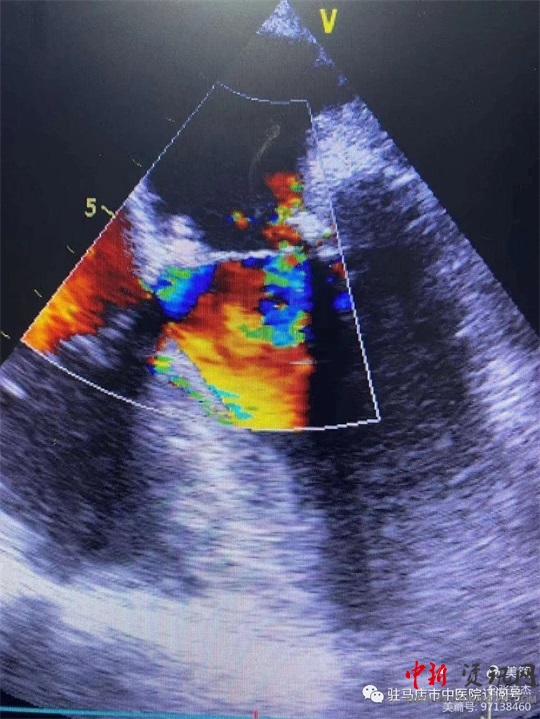

復(fù)跳后經(jīng)食道心臟超聲,二尖瓣功能較術(shù)前明顯改善。